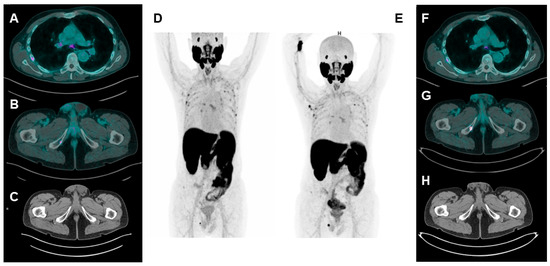

| Fendler et al. [9] | Germany/USA 2019 | Retrospective, investigator-initiated, multicenter | 200 | Detection rate of lesions, on a per-patient basis, by PSMA-PET. | 68Ga-PSMA-11/ 18F-DCFPyL | Almost all cases showed positive findings in spite of negative conventional imaging: 55% of patients had distant metastases (M1). |

| Fourquet et al. [7] | France/2020 | Retrospective | 31 | Impact of PSMA PET in the restaging of nmCRPC patients. | 68Ga-PSMA-11 | PSMA-PET detected at least 1 focus of tracer uptake in 90% of cases and changed clinical management in 87% of cases. |

| Wang et al. [17] | China/2021 | Prospective, observational | 37 | To assess metabolic heterogeneity (PSMA+/FDG− disease) in early progressive nmCRPC. | 68Ga-PSMA-11/ [18F]FDG | A total of 114 lesions were detected among 29 out of 37 nmCRPC patients. N+/M+ disease was detected in 73% of patients. |

| Weber et al. [18] | Germany/ 2021 | Retrospective | 55 | To investigate the ability of PSMA PET to detect metastatic lesions in early CRPC. | 68Ga-PSMA-11 | PSMA PET resulted in positive results in 75% of patients, of whom 45% had M1 status. |